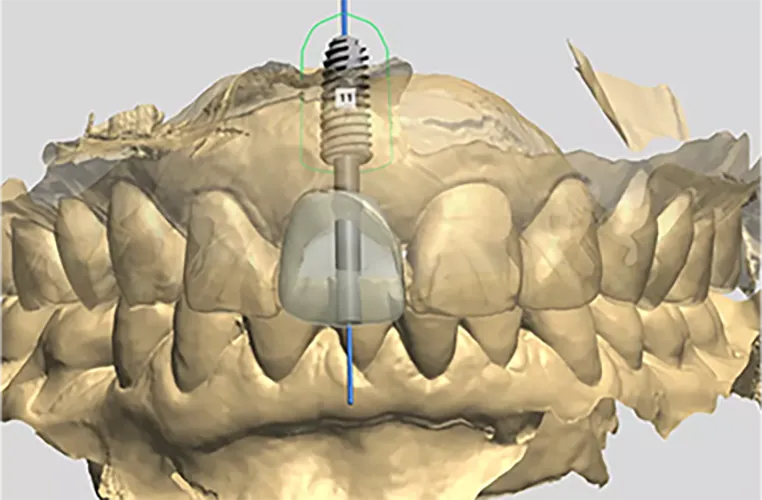

サージカルガイドと専用のドリルを用いることで、インプラントを事前に撮影したCT画像で設定した理想的な位置に、正確にインプラントを埋めこむことが可能となります。

サージカルガイドを用いることでインプラントの埋める位置を精緻に決定し、3次元的に完璧な軸方向へのインプラント治療が可能となります。この軸方向の問題は起きてから対処すると取り返しがつかず、最悪の場合、インプラントを撤去しないといけないこともあるのです。

このようなことが起きないように完璧な手術で、術後の咬み合わせまでしっかりと適合させることができるのが、サージカルガイドです。

従来の手術法では、埋入位置のエラー、埋入深度のエラー、埋入方向のエラーなどのリスクがありましが、サージカルガイドを使用した手術なら、

これらのリスクの心配なく、審美的にも身体的にも身体と調査させることができます。